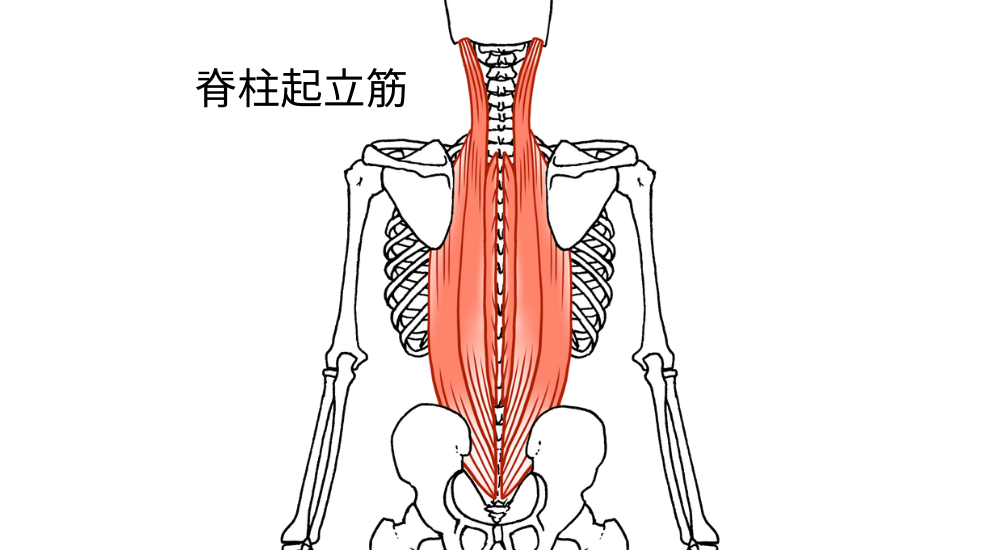

- 脊柱起立筋:

背骨に沿って走行し、姿勢の維持に重要な筋肉。猫背・反り腰などで常に緊張しやすいです。